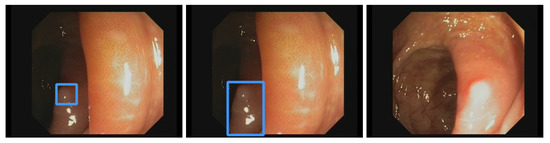

Additionally, the polyp-detection system was publicly funded and developed by computer engineers and endoscopists in the same workgroup to ensure high-quality polyp detection. Figure 1 shows the results of the polyp-detection system. To overview existing work and properly allocate our paper in the literature, we describe a brief history from general polyp detection with handcrafted features to state-of-the-art polyp detection with deep learning techniques.